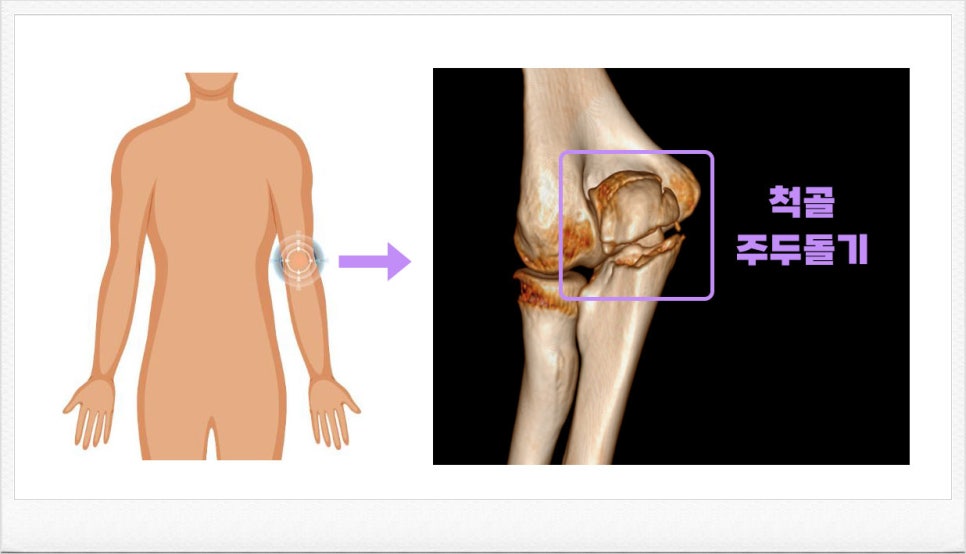

주두돌기는 팔꿈치 뒤쪽, 팔을 구부렸을 때 가장 튀어나오는 뼈 부위입니다. 흔히 부딪히거나 넘어지면서 팔을 짚는 충격으로 손상이 되는데요, 주두돌기 골절은 팔꿈치 골절 중 약 10% 정도로, 상당한 비율을 차지합니다.

▼ 진단명, 진단 코드 · 척골 주두돌기 골절 · S52020